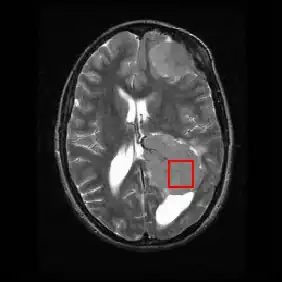

Neural Imaging

Neuroimaging contains a variety of techniques to directly or indirectly image of the structure, function/pharmacology of thenervous system. It is a relatively new fields within medicine, neuroscience and psychology.[22] Physicians who specialize in the performance and interpretation of neuroimaging in the clinical setting are neuroradiologists.

Neuroimaging is classified into two categories:

- Structural imaging, which deals with the structure of the nervous system and the diagnosis of gross (large scale) intracranial disease (such as tumor), and injury.

- functional imaging for diagnosing metabolic diseases and lesions on a finer scale (such as Alzheimer's disease) and for neurological and cognitive psychology research and building brain-computer interfaces.

| Imaging Modality | Technique | Advantage | Comparison | Image |

|---|---|---|---|---|

| General radiography | Passes electromagnetic radiation(x-rays) through body which either is absorbed by dense objects(eg.bones) or passes through to a detector on the other side of the body, creating an image | Rapid, cheap, nonvasive | minor radiation exposure | |

| CT | Passes x-rays through the body while the detector and x-ray generator rotate around the body, generating various images/slices of the body in each plane | Rapid,noninvasive | Radiation Exposure | |

| fMRI | Tracks blood flow and oxygen levels which proper neuronal activity;often superimposed on structural MRI slices for orientation; can be linked in time with MMG | Noninvasive, no radiation injection, or ingestion required | Blood flow/oxygen depend on the cardiovascular level response; results in temporal delay between stimulus and output | |

| MRI | Uses magnetic field and radio waves to create images of variably aliened and misaliened hydrogen ion in the tissue | Noninvasive, precise, no radiation | Expensive, no permission in patients with metal biomedical implants or clips/stents or severe clastrophobia |

|

| DTI | Tracks water movement along neural pathways as proxy for neural activity;simultaneously | Noninvasive, no radiation, injections, or injestions required. | Interpretation can be complex |

| PET/SPECT | Uses radio isotope(ingested or injected; measures uptake of the radioisotope; allows in vivo monitoring of molecular changes; used with structural imaging | Molecular changes visible in real time | Radioactive substance, minor radiation exposure |